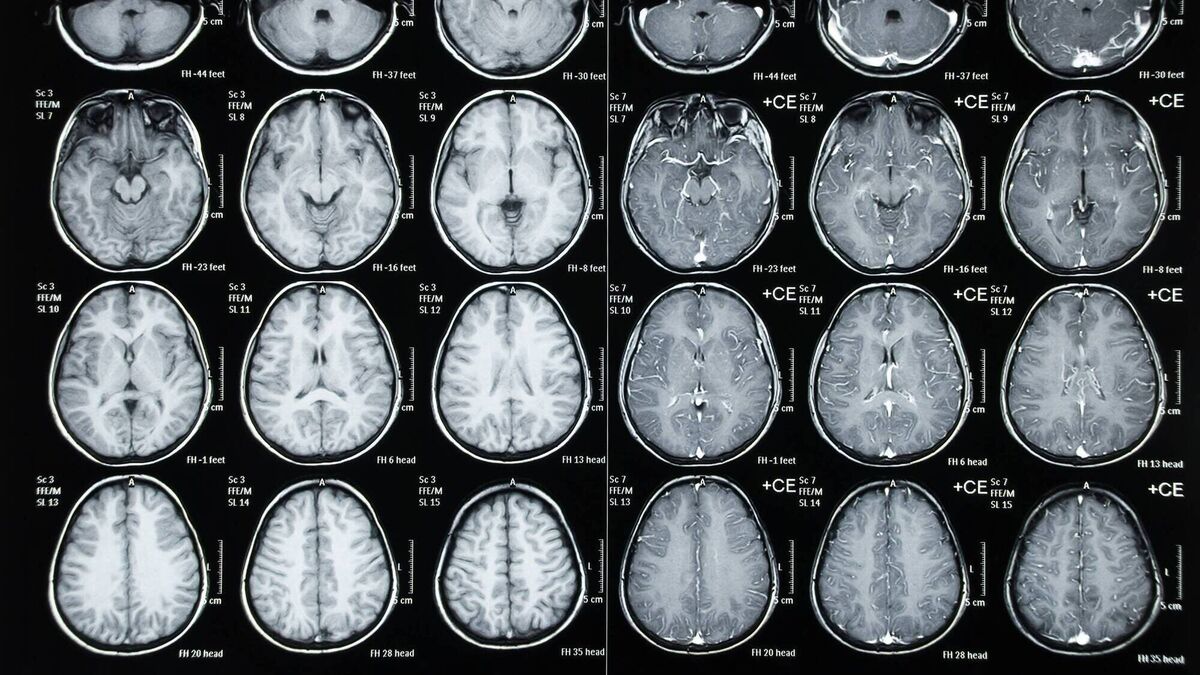

It was heartbreaking and alarming enough when ageing footballers, so many of England World Cup winners from 1966 among them, and American football players on another continent and from another world were the ones suffering. Now it is former rugby players in their 30s and 40s in these islands being diagnosed with early-onset dementia.